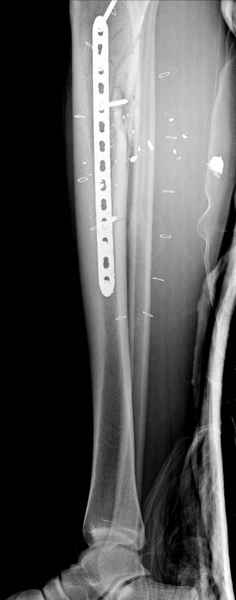

1 неполный перелом большеберцовой кости перкутанная пластина

Имя     : 1 GSW tibia.jpg

Тип     : image/jpeg

Размер  : 16233 байтов

Описание: отсутствует

Url     : http://weborto.net:8080/pipermail/ortho/attachments/20090726/b21ae3ea/attachment-0011.jpg